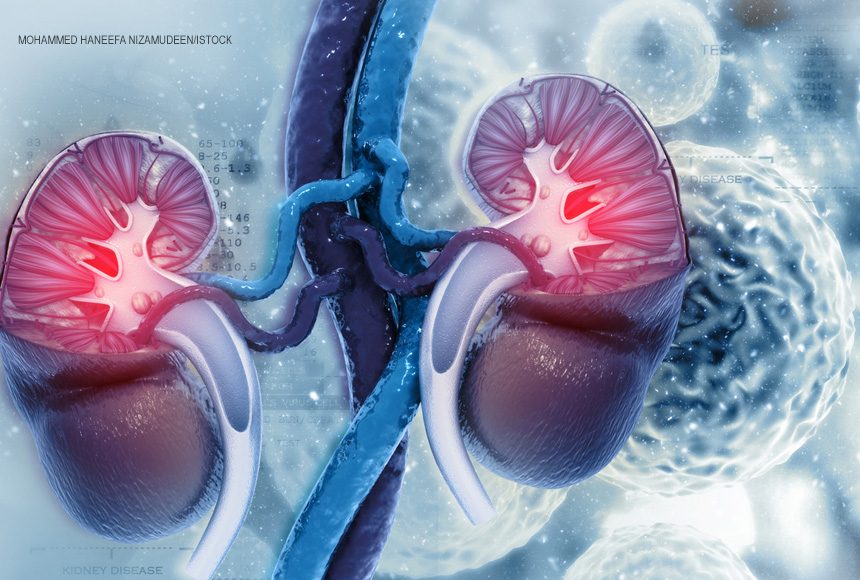

Uma perspectiva de tratamento inovadora, que preserva o rim, pode ser nova aliada no combate ao tumor urotelial do trato superior, que se localiza no revestimento interno do rim, ureter ou bexiga. Estudo em fase 1 mostrou evidências promissoras da terapia fotodinâmica, com alvo vascular com agente fotossensibilizador, para eliminar o tumor com uma ou, no máximo, duas sessões. A informação é do urologista Lucas Nogueira, um dos responsáveis pela pesquisa feita pelo Memorial Sloan-Kettering Cancer Center (MSKCC), em Nova York, onde é pesquisador visitante.

A terapia usa uma substância derivada da clorofila, chamada de padeliporfina, que na presença de luz de diodo com comprimento de onda de 753 nanômetros (nm) no local, provoca uma reação trombótica matando o tumor por falta de oxigenação, além de estimular o sistema imunológico contra o câncer. “É como se ocorresse um infarto naquela região. O tumor necrosa e desaparece em um período de até 30 dias”, explicou o médico.

De acordo com o pesquisador, os dados do estudo fase 1, feito em 16 pacientes do Memorial Sloan-Kettering Cancer Center, mostram que em 64% dos casos o tumor não foi detectado após 30 dias e em 29%, foi preciso fazer uma segunda sessão. Dos que fizeram a segunda sessão, 67% tiveram a remissão completa do tumor. Após 11,5 meses de seguimento, 93% dos pacientes mantiveram o rim que tinha sido afetado pelo câncer, e a função renal não foi significativamente afetada.

Segundo Lucas Nogueira, o câncer urotelial do trato alto é duas vezes mais comum em homens, principalmente a partir dos 60 anos. Entre os principais fatores de risco estão tabagismo, história de câncer de bexiga e exposição ocupacional a agente químico (petroquímica, plástico, tinta) e ser portador da Síndrome de Lynch.

O câncer urotelial de trato alto é assintomático, de difícil diagnóstico, sendo descoberto muitas vezes em estágio avançado devido ao aparecimento de sangue na urina. Dor na lateral do corpo, provavelmente devido à obstrução da urina, é a segunda causa de descoberta da doença. Outros sintomas são aumento da frequência urinária, urgência urinária e dor ao urinar.